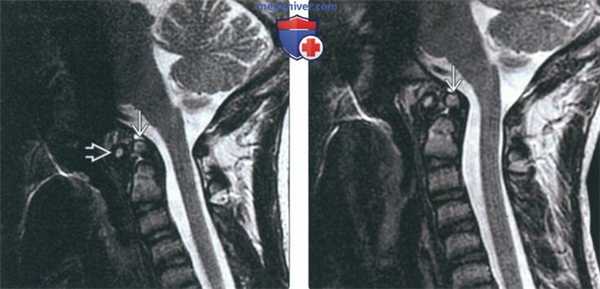

(Слева) На сагиттальной МРТ (Т2 ВИ) в положении сгибания определяется переднее положение дистопической зубовидной костив относительно С2. Расстояние между передней дугой С1 и зубовидной костью сохранено; определяется нарушение положения зубовидной кош относительно С2 по сравнению с изображениями в нейтральном положении и при разгибании (атланто-аксиальная нестабильность).

(Справа) На сагиттальной MPT (Т2 ВИ) в положении разгибания у этого же пациента положение зубовидной кости обычное. На сагиттальной МРТ (Т2 ВИ) в положении сгибания определялось переднее смещение зубовидной кости, свидетельствующее об атланто-аксиальной нестабильности.